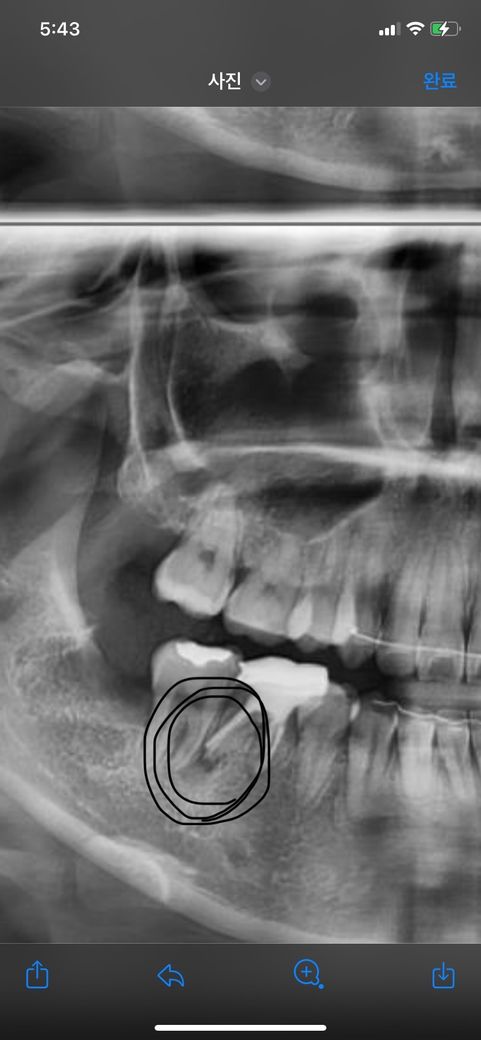

이거 염증 맞나요? 염증이 충치인가요? 떼운이에 이렇게 됫는데 너무아프네요 ㅠ 빨리 치료해야겠죠? 병명은 뭔가요? 그리고 치료비용 간단하게 알려주세요

• 1번 째 사진

지금 단 브이에 염증이 생긴 것으로 보입니다. 치근단 무의 염증은 보통 신경관 내부의 감염으로 인해서 생기게 됩니다. 재신경치료 등을 통해서 염증을 없애는 걸 시도해 볼 수 있습니다. 치아뿌리 금리가서 생긴 염증이라면 치아를 발치해야 하는 경우도 발생할 수 있습니다.

치아 뿌리 끝에 염증이 있는 것이 보이며 재신경치료를 하거나 잇몸의 문제면 잇몸치료를 해봐야 겠습니다.

치아 뿌리끝에 염증이 잇는거 같습니다. 일단은 잇몸치료를 해보시는게 좋을것같습니다 잇몸치료는 의료보험이 적용되는거기 때문에 1-2만원 나올꺼에요.